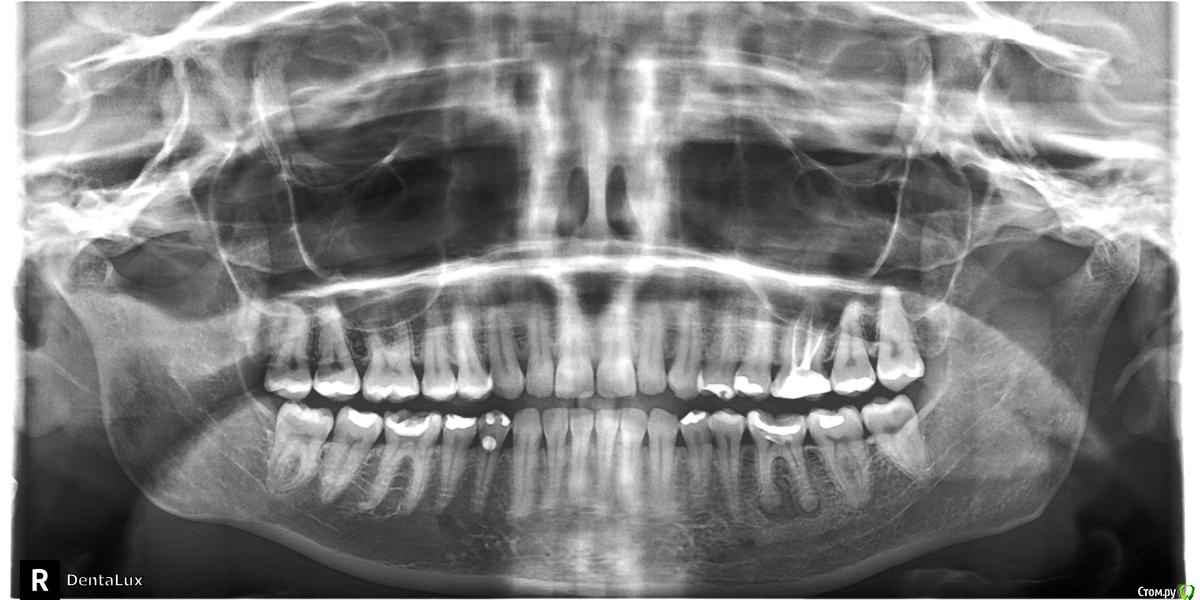

miep Опубликовано 14 августа, 2017 Поделиться Опубликовано 14 августа, 2017 Зуб был депульпирован в конце февраля 6 ка левая верхняя. Чувствительность зуба сохраняется до сих пор. при надавливание со стороны щеки чувствую неприятные ощущения.Ощущения пропадают после несколько раз надавливаний но потом возвращается...по снимку врачи не видят ничего такого. В 6 ке нижней правой было 4 канала. может и там тоже 4 но не нашли? КТ сделать пока не могу....сделала панарамный. Может вы что увидите?Что можно сделать? Ссылка на комментарий

red_butler Опубликовано 16 августа, 2017 Поделиться Опубликовано 16 августа, 2017 неужели по снимку ничего никто сказать не может?так по Вашему снимку ничего конкретного сказать нельзя. Ссылка на комментарий

IvanK Опубликовано 17 августа, 2017 Поделиться Опубликовано 17 августа, 2017 надо сделать кт.. и заняться 36 Ссылка на комментарий

IvanK Опубликовано 17 августа, 2017 Поделиться Опубликовано 17 августа, 2017 понимаю, но хотя бы от чего такое может быть. еще и нос переодически на этой стороне закладывает. ЛОР ничего не нашла. без КТ - гадание это как ремонт авто по фотографии.. Ссылка на комментарий